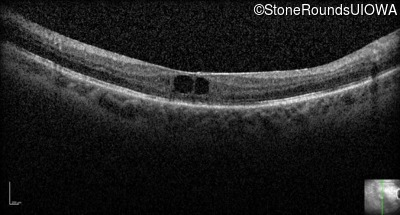

Optical Coherence Tomography - Right - 20/50 +2

Exemplar / OCT Stack